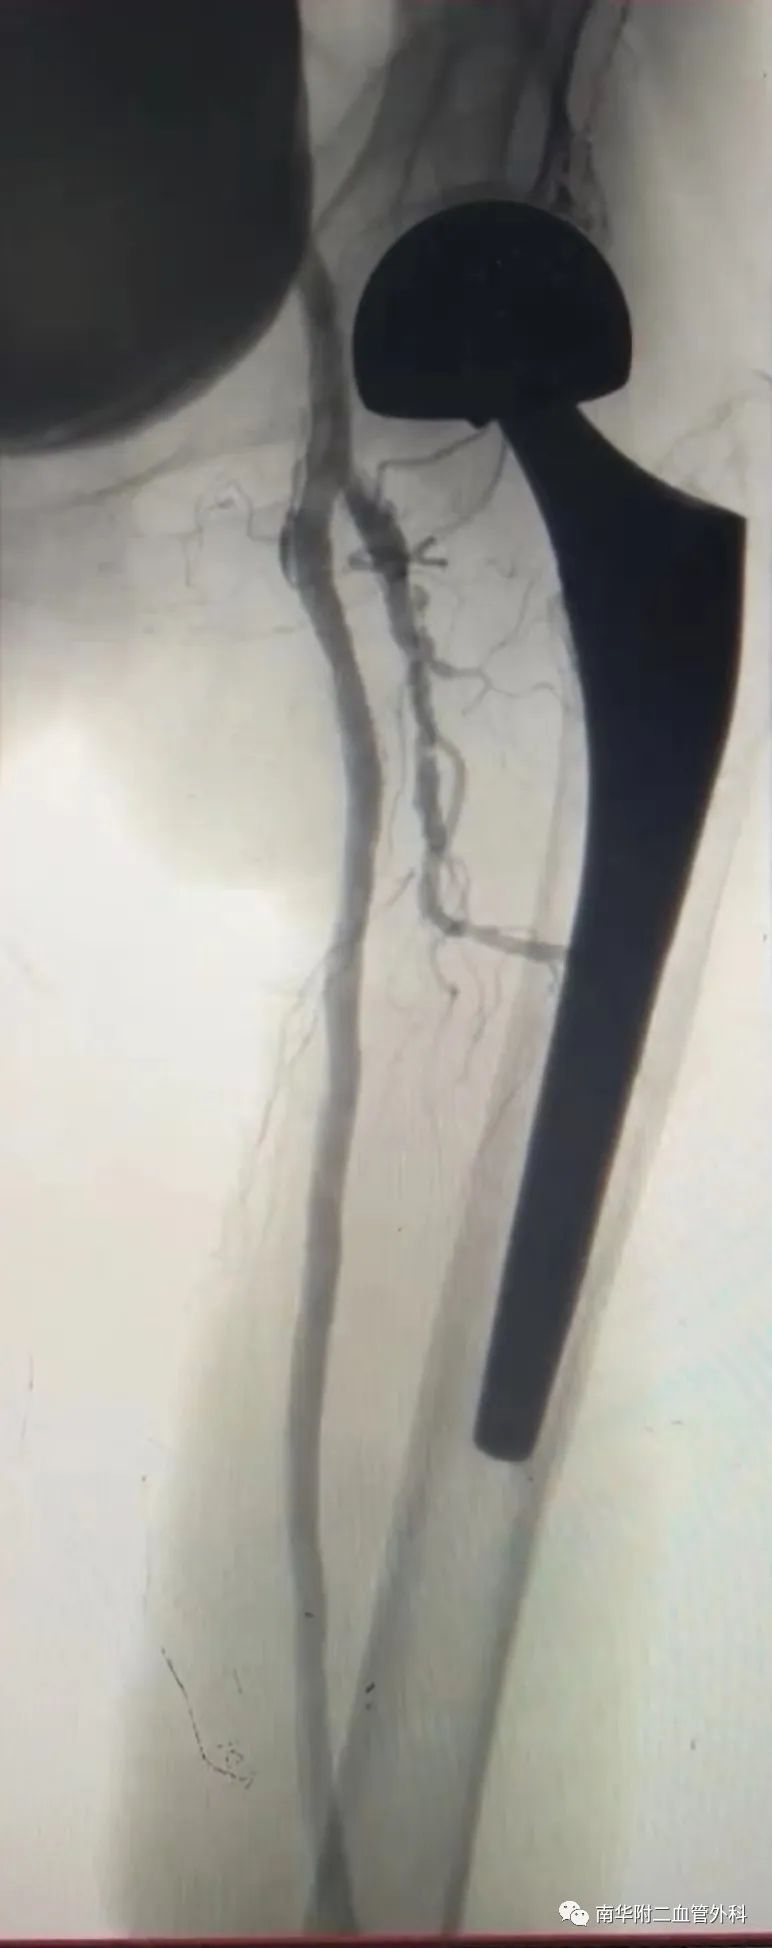

图片:影像学检查结果

在结合影像学检查结果,对丁奶奶病情进行具体分析,并与患者及家属进行详细沟通后,熊国祚教授决定先为患者进行左侧经皮动脉内球囊扩张术,为患者开通血管,术后预期患者可以重新自主行走,告别间歇性跛行,同时避免截肢危险。对病情较轻的右下肢,稍后再进行治疗计划。

熊国祚教授团队为患者先行实施置管溶栓术,数日后再为患者实施经皮动脉内球囊扩张术,手术用时近三小时,顺利完成。术后,患者左侧皮温明显转暖,左下肢缺血情况得到明显改善。

图片:术后造影效果